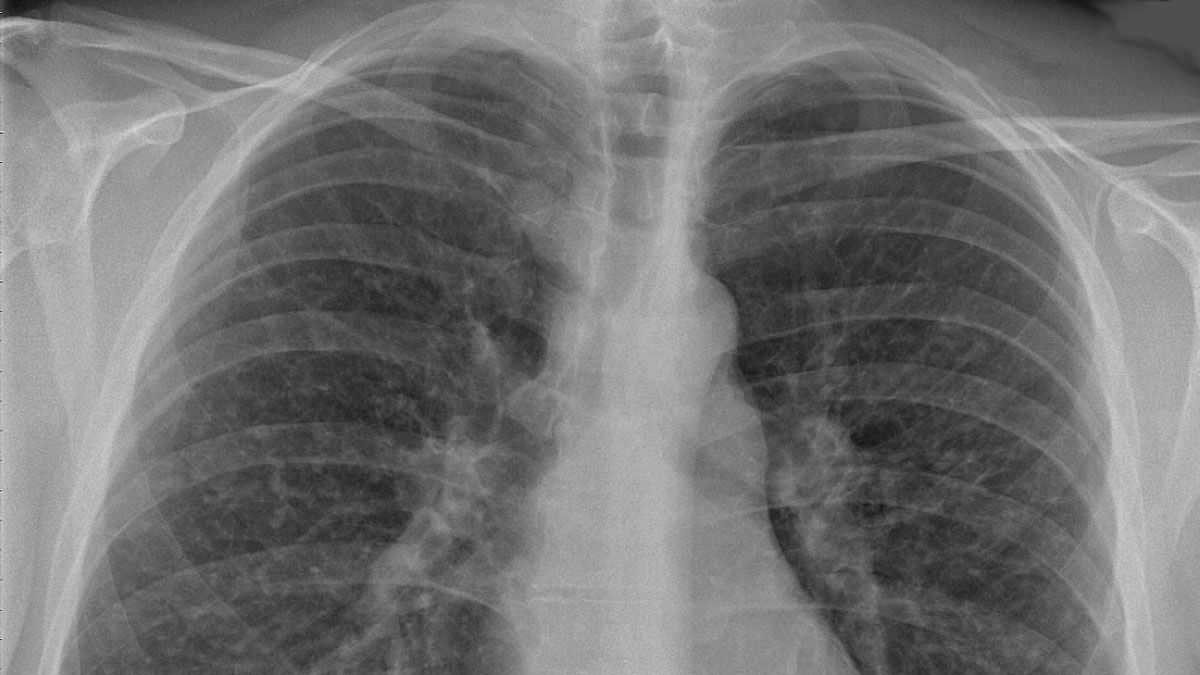

"La neumonía bilateral puede detectarse por una tomografía o radiografía de tórax", señaló la neumonóloga Ana María Putruele, Jefa de Neumología del Hospital de Clínicas José de San Martín.

El diagnóstico de la neumonía bilateral se hace a través de una radiografía del tórax. También es necesario realizar una exploración física y, una vez que se establece el diagnóstico, generalmente hacen falta otras pruebas para ver el tipo de gérmenes y el tipo de severidad.